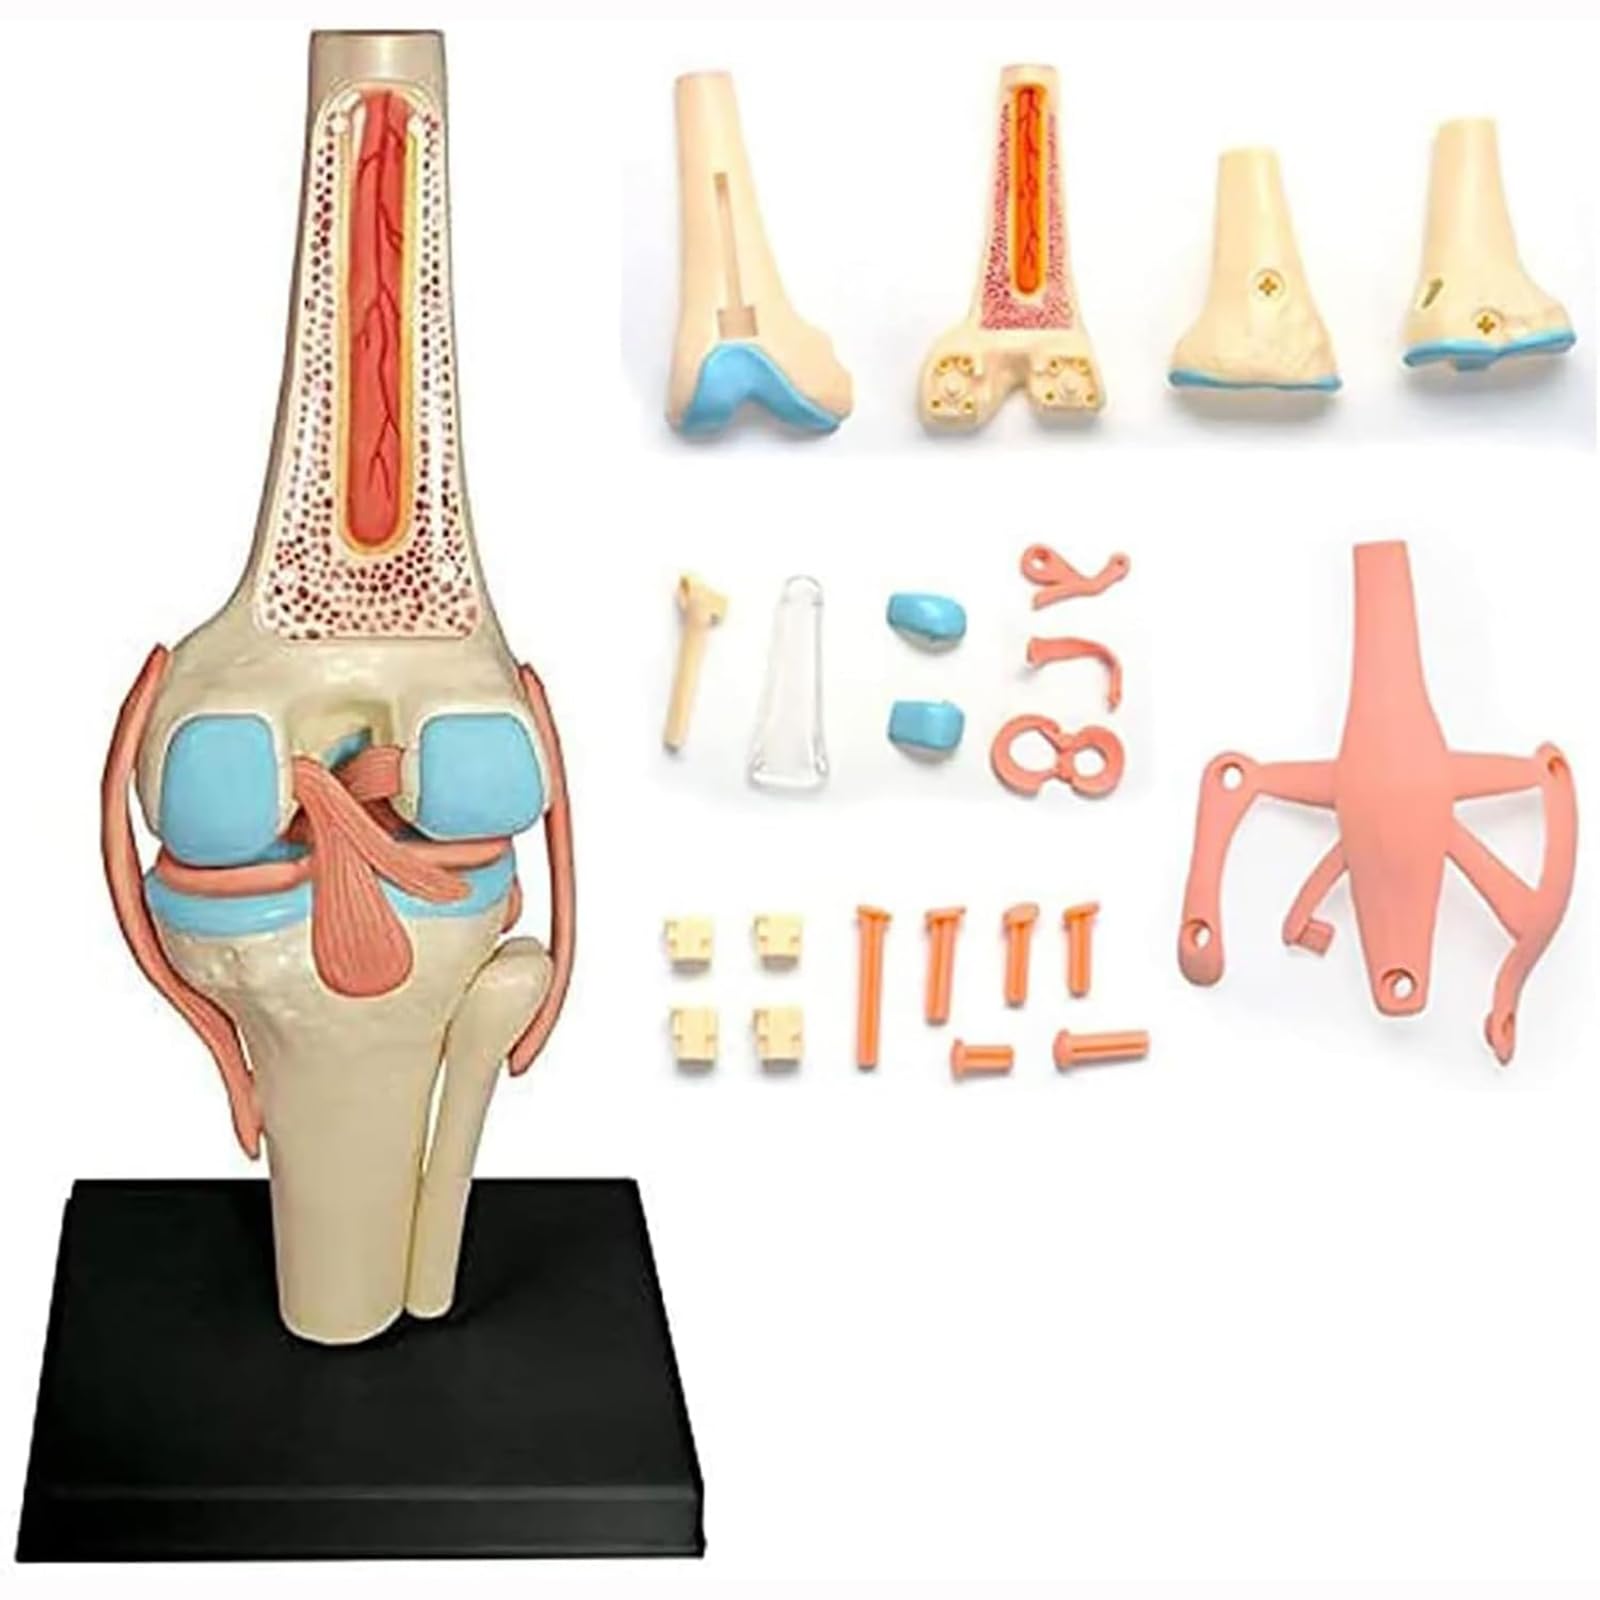

UNbit Anatomical Model of Human Knee Joint Organs 4D Model of Human Knee Articulation 23 Detachable Parts Model of Medical Teaching for Medical Education

UNbit Anatomical Model of Human Knee Joint Organs 4D Model of Human Knee Articulation 23 Detachable Parts Model of Medical Teaching for Medical Education

This anatomical model aids in the study of human biology and anatomy by providing a hands-on, 3D representation of the knee joint.